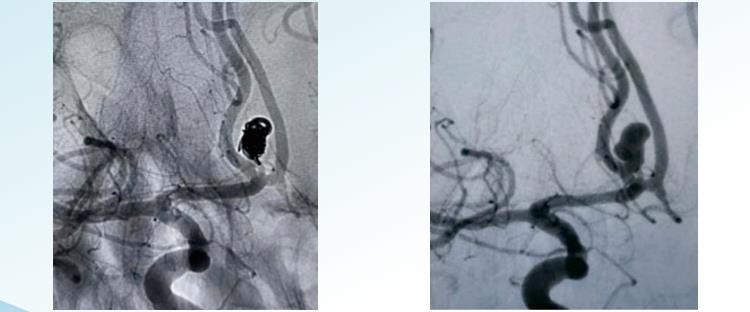

RenovaTM3D avtakbare spoler

RenovaTMSpiralformede avtakbare spoler